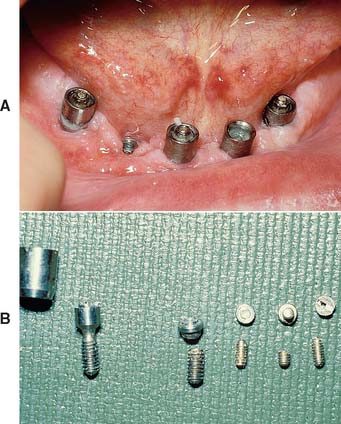

Fig. 13-1 Implant-supported fixed prosthesis. Four dental implants (A) supporting a fixed dental prosthesis (B).

Fabrication of screw-retained prostheses requires a number of components unique to implant dentistry. For less experienced clinicians, the large number of parts included within one system might create problems. This section describes in generic terms the component parts typically needed to restore an osseous integrated implant. There are many dental implant systems, and although all the major components are available for each system, many differ slightly in specific design and materials. The basic steps for implant restoration fabrication are described in Figure 13-21.

During the healing phase after first-stage surgery, a screw is normally placed in the superior aspect of the fixture. It is usually low in profile to facilitate the suturing of soft tissue in the two-stage implant or to minimize loading in the one-stage implant (Fig. 13-23). At second-stage surgery, it is removed and replaced by subsequent components. In some systems the screw is made slightly larger than the diameter of the implant, which facilitates abutment placement by ensuring that bone does not grow over the edge of the implant. The implant surgeon should always be sure that the healing screw is completely seated after stage-one surgery to prevent bone from growing between the screw and the implant. If this occurs, removing the bone may damage the superior surface of the implant and affect the fit of subsequent components.

Fig. 13-23 Healing screw (arrow) in place during the initial implant-healing phase. Soft tissue is sutured over the implant. A removable prosthesis can be worn over this area during healing.

Interim abutments are dome-shaped screws placed after second-stage surgery and before insertion of the prosthesis. They range in length from 2 to 10 mm and project through the soft tissue into the oral cavity. They may screw directly into the fixture or, in some systems, onto the abutment immediately after second-stage surgery. Those that screw onto the abutment are commonly referred to as healing caps (Fig. 13-24). Both interim abutments are made of titanium or titanium alloy. In areas where esthetics is paramount, healing should be sufficiently completed around an interim abutment to stabilize the gingival margin. At this time, abutments of appropriate length are selected to ensure that the metal-porcelain interface of the restoration will be located subgingivally. In areas where tissue esthetics is not crucial, adequate healing for impressions usually takes 2 weeks. In esthetic zones, 3 to 5 weeks may be required before abutment selection. In addition, knowing the length of the healing cap can expedite abutment selection.

Fig. 13-26 A, Interim abutments projecting through the soft tissue. B, Implant restorations supported by standard abutments that allow easy access for oral hygiene.